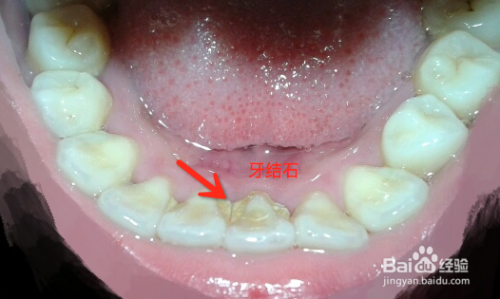

采用超声波清洗牙结石。我去医院洗过牙,一般牙齿牙结石比较多的医生会建议你洗牙,像牙齿偏黄想要变白的建议不要去洗牙,因为洗牙只是对我们平时牙刷清洁不到位的地方进行清洁。超声波洁牙利用的是高频率震动的方式把牙齿周围的牙结石给清洁干净,是不具备美白牙齿的功能的!